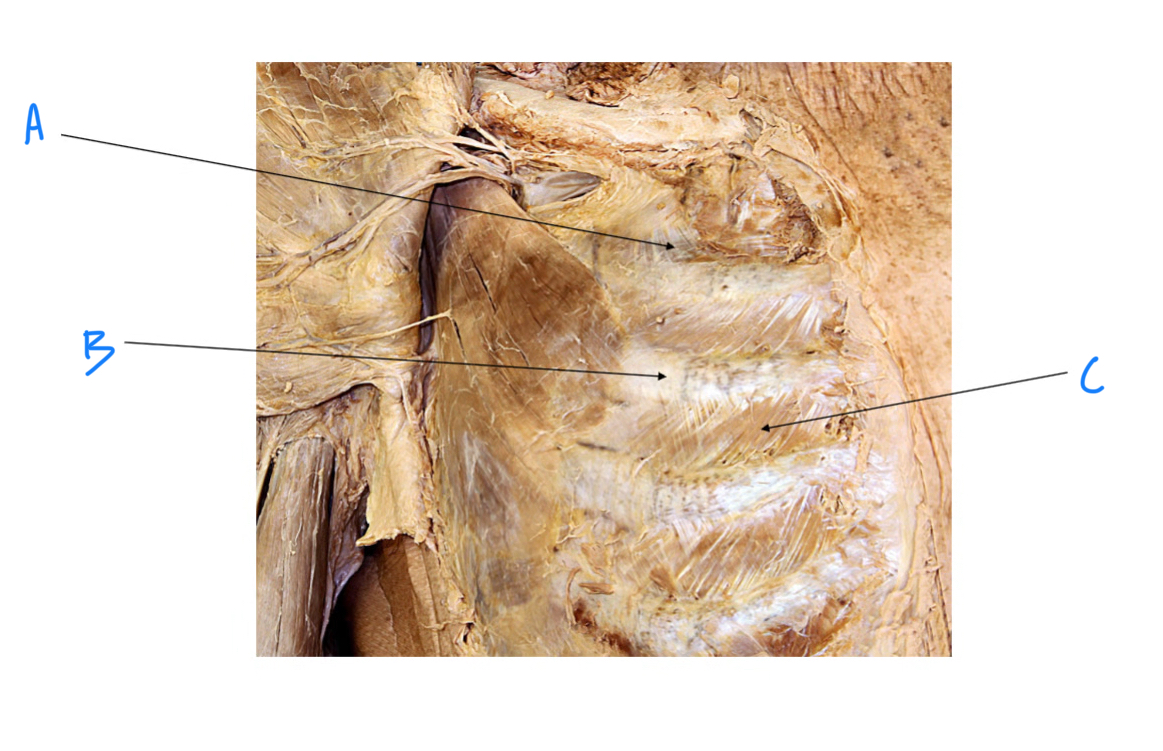

A. Identify structure

Transverse foramen; Vertebral a.

B. Identify structure; What goes through this feature?

Transverse process

C. Identify structure